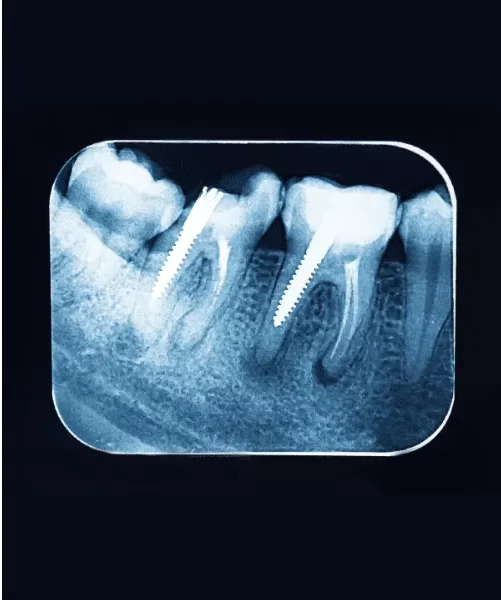

Planning Root canal X-ray for Extractions, Implants, or Surgeries

- What it does: X-rays give a detailed view of the tooth’s position and the surrounding bone and tissues.

- Why it’s important: This information is crucial for safely planning procedures like tooth extractions, dental implants, or other oral surgeries.

- How it helps: With X-rays, the dentist can plan the procedure accurately, reducing risks and improving outcomes.